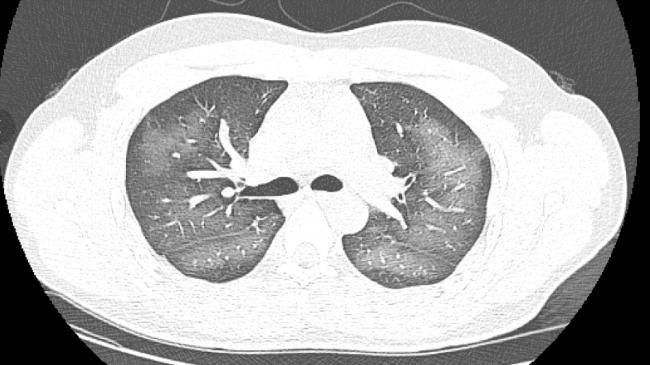

Sau khi kiểm tra, chụp CT phổi cho thấy phổi của Li Lin có một vùng màu trắng khá rộng, là biểu hiện của sự tổn thương. Bác sĩ Zhang Xiuping, trưởng Khoa X-quang của Bệnh viện số 3 Trường Sa cho biết "phổi trắng" thường chỉ sự xuất hiện của bệnh viêm phổi nặng.

Chụp CT phổi của nam thanh niên thấy trắng xóa một mảng lớn.